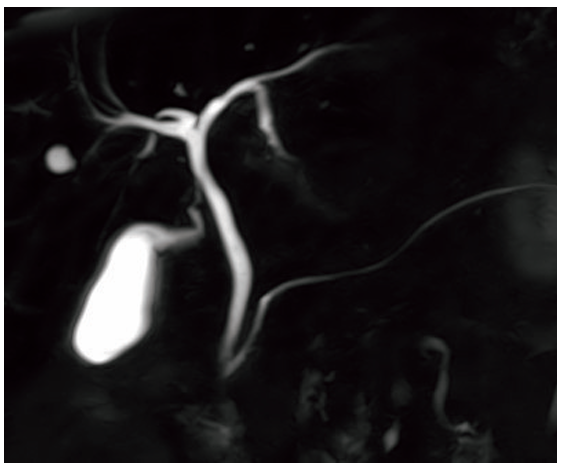

MRCP像を示す。

正しいのはどれか。

- T1強調像である。

- 胆囊管は描出されていない。

- ガドリニウム造影剤を用いる。

- 総胆管結石は高信号に描出される。

- 消化管内の液体信号を消すために陰性造影剤を用いる。

- T2強調像である

- 胆囊管や胆嚢、膵管などが描出されている

- 造影剤を使用せずに描出できる

- 総胆管結石は低信号に描出される

答え 5